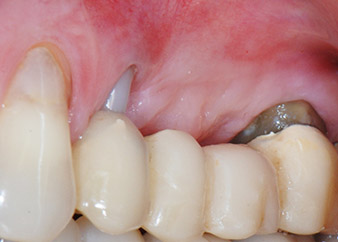

След един месец, в деня на операцията, болката и възпалението в зъб 24 е минимално, но подвижността в Miller class 2 е на лице. След отваряне на ламбата и почистването на периапикалната и перирадикуларната тъкани, обхватът на костния дефект стана очевиден (Фиг. 2 и 3).

В букалния корен, цялата вестибуларна и дистална кост липсва. Захващането е значително ограничено до палатиналния корен, подчертавайки предварително лошата прогноза. Зъб 27 също откри намалено хоризонтално захващане и минимално апикално разреждане (Фиг. 1) без клинични симптоми.

Въпреки това, ние се придържахме към първоначалния си план да запазим и двата зъба като абатмънти за временен мост по време на 6-месечната остеоинтеграция на имплантите. При повторна интервенция, ситуацията трябва да се преразгледа. Първо, в опит да се овладее ендо-перио проблема, останалата повърхност на зъба е внимателно обработена с пиезохирургично оборудване (Piezomed, W&H, използван с накрайник S1 под формата на шпатула, първоначално проектиран за ерозия на латералната синусна стена) (Фиг. 4).